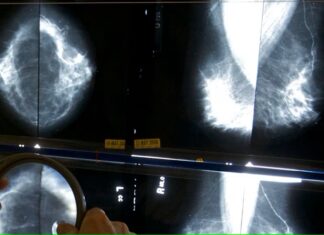

¿Se puede confiar en una mamografía para identificar el riesgo de enfermedad cardíaca?

Hoy en día, cuando las personas se hacen su mamografía anual, algunos radiólogos les preguntan algo desconcertante. Además de analizar la prueba en busca...